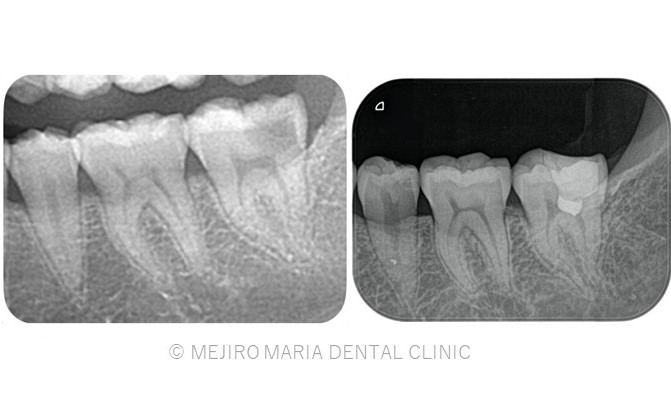

東京 目白マリア歯科 精密根管治療の症例

【歯根端切除術】

根管治療を行っても良くならない場合の外科的歯内療法

精密根管治療を施しても治癒に至らない場合、もしくは、被せ物を外すことが困難な場合(装着して間もない被せ物など)は歯根端切除術にて根尖性歯周炎を治癒に導くことが可能です。現代の歯根端切除術の成功率は90%以上で、破折していない歯であれば保存することが可能です。しかし、外科処置なのでリスクも当然あります。当院では精密根管治療初回カウンセリングにてご自身の歯の状態や診断から精密根管治療(歯内療法)後のリスクをお話した上で、治療介入を行うか患者様に決めていただいております。